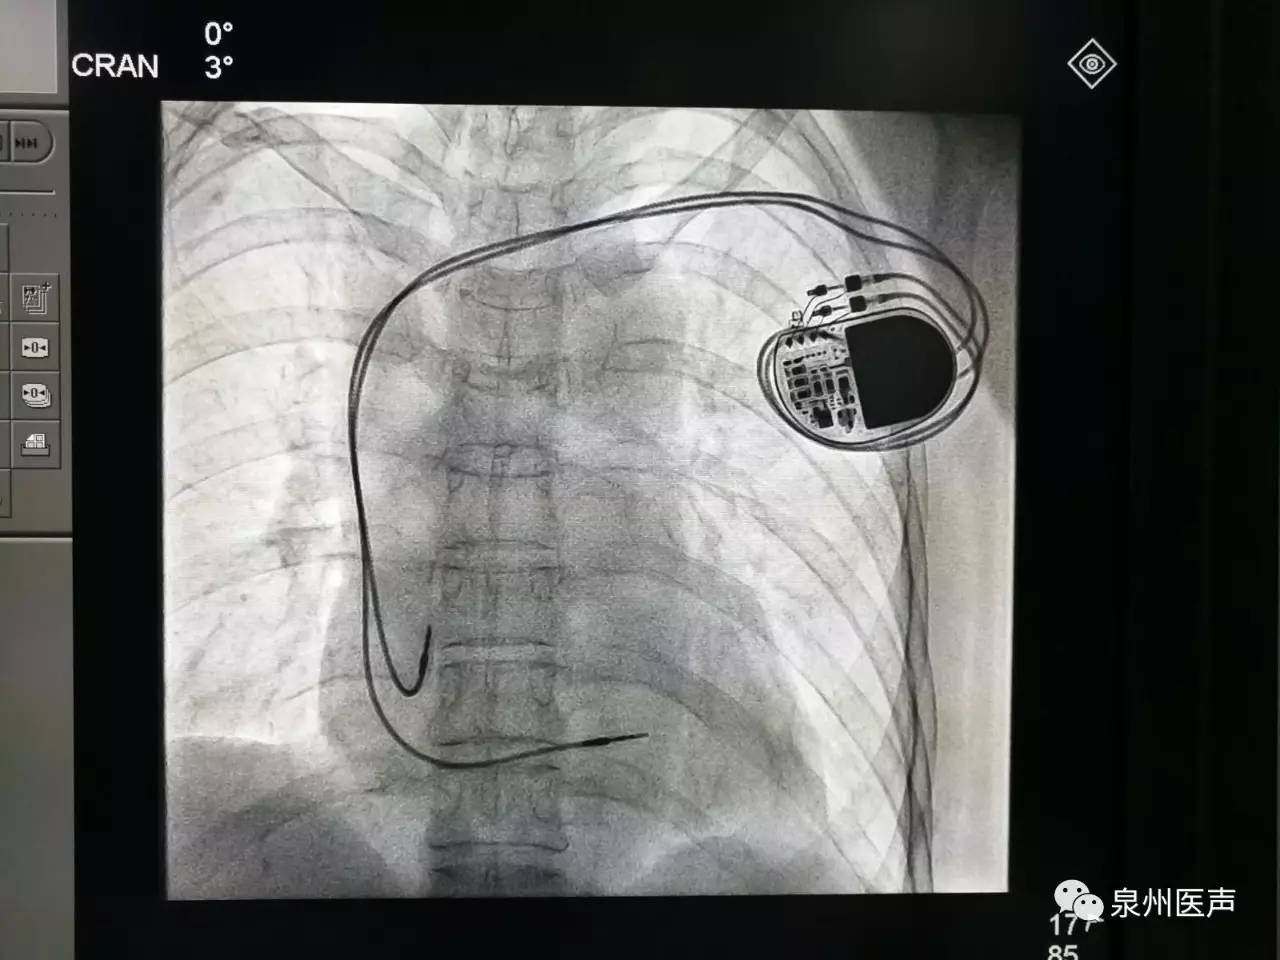

微創(chuàng)、樂普、先健填補(bǔ)國(guó)產(chǎn)起搏器市場(chǎng)空白,釋放哪些信號(hào)?

世界最小起搏器,正式進(jìn)入中國(guó)市場(chǎng)!

最高級(jí)別!美敦力緊急召回1.3萬(wàn)個(gè)雙腔植入式心臟起搏器!

美敦力公司因可能的電路問(wèn)題,將召回超過(guò)1.3萬(wàn)個(gè)雙腔植入式心臟起搏器。FDA確認(rèn)此次召回為最嚴(yán)重的一類召回,使用該醫(yī)療器械可能或?qū)⒁饑?yán)重健康危害。

心臟起搏器的日常護(hù)理

心臟起搏器出院的宣教,是心內(nèi)科醫(yī)護(hù)人員不容忽視的一項(xiàng)工作